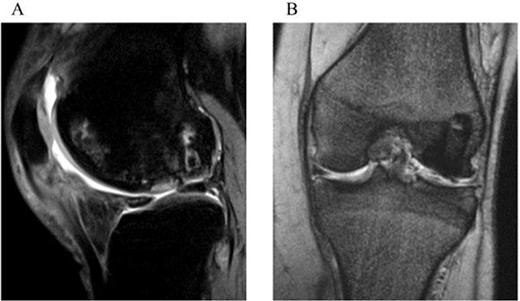

A 31-year-old female with SLE, who had been receiving oral steroid therapy since the age of 16, presented with severe pain in her left knee without any particular trigger. Physical examination showed local swelling and effusion in the left knee, and the passive ranges of motion for both extension and flexion were limited to −30° and 130°, respectively. Ligamentous instability or apparent malalignment was not noted. Radiographic examination of the knee showed flattened contour of the lateral femoral condyle and irregularity of the articular surface (Fig. 1a). MRI showed osteonecrosis extending from the lateral femoral condyle to the femoral trochlea, whereas a tear of the lateral discoid meniscus was also identified (Fig. 1b and c). A sagittal fat-saturated T2-weighted image of the contralateral right knee also showed osteonecrosis lesion in the lateral condyle (Fig. 1d). Based on those clinical and image findings, diagnoses of steroid-induced osteonecrosis of the femoral condyle and a tear of the lateral discoid meniscus were made. An urgent arthroscopy was performed as the patient was experiencing severe knee pain and limited extension of the knee because of detached osteochondral fragments and discoid meniscal tear. First, the ganglion connected to the anterior horn of the lateral discoid meniscus was resected, and a partial meniscectomy (meniscoplasty) was performed. A 35 × 45 mm cartilage defect was found in the lateral femoral condyle, and the detached osteochondral fragments were removed (Fig. 2a and b). After the removal of detached chondral lesions under arthroscopy, the limitation of the ROM and severe pain was resolved. However, a large osteonecrosis lesion with osteochondral defects remained, which presumably lead to secondary osteoarthritis. Therefore, OAT was planned as a second-stage surgery. At the OAT procedure, the contralateral knee could not be used for graft harvest because of the presence of osteonecrosis in the femoral condyle. Therefore, only two 10-mm diameter osteochondral grafts could be harvested from the non-weight bearing area of the medial femoral condyle in the ipsilateral knee, and then inserted into the recipient site (Fig. 3a and b). Since only part of the lesion area could be replaced by the host tissue, microfracture was performed in the remaining lesion. Postoperatively, ROM exercise was started immediately, whereas weight bearing was not permitted for the initial 4 weeks and gradually returned to full weight thereafter.

Intraoperative findings during OAT procedure. (a) Cartilage defect at the lateral condyle in the left knee. (b) Two osteochondral plugs transplanted into the recipient site.